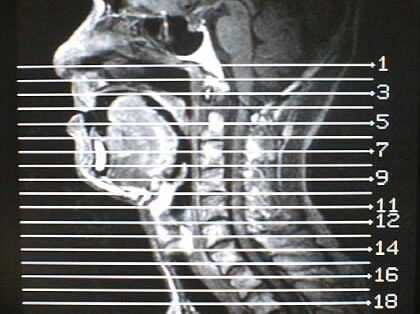

MRI画像比較

入院当時MRI画像③

入院3か月後癌消滅MRI画像③